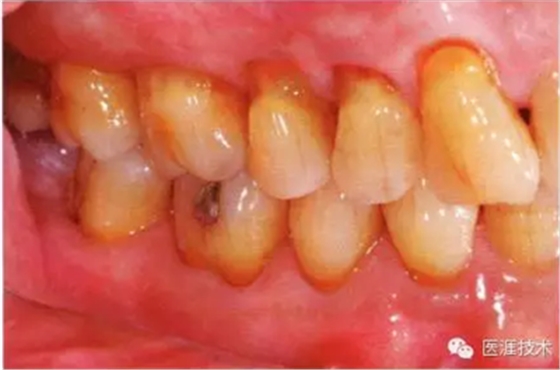

55歲牙周炎男性的臨床照片

55歲男性抽煙患者(1天20支、抽煙35年)。菌斑控制得不好。通過牙周探診,全頜有4~9mm的牙周袋,有1~3度的根分叉部病變。通過X光片觀察,上頜前牙中度牙槽骨吸收,其他地方有中度牙槽骨吸收。受吸煙影響,牙齦纖維性肥厚,呈紅黑色。牙齦幾乎沒有浮腫和發(fā)紅,所以這個病例是從外觀上無法預測病癥嚴重程度的病例。